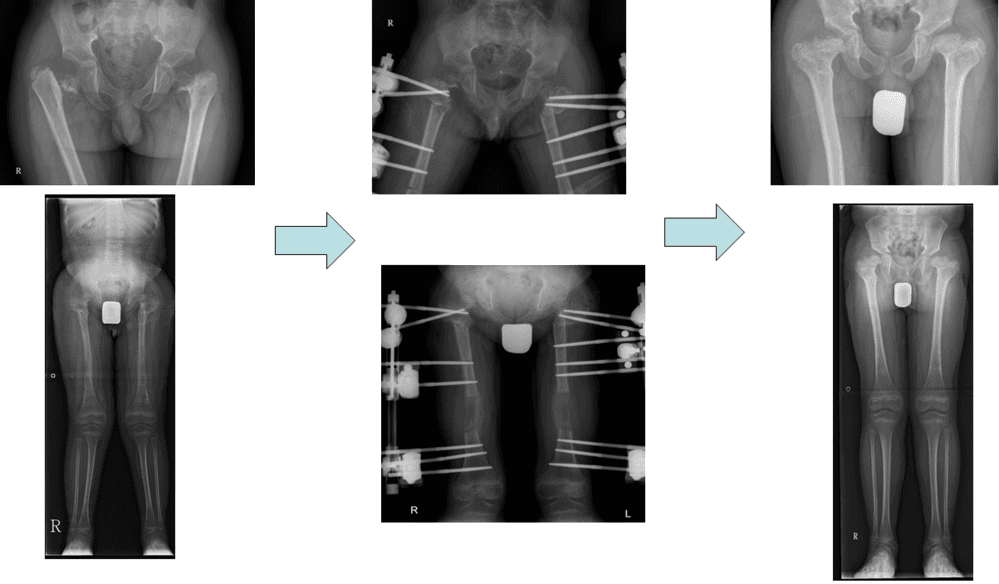

척추골단이형성증 환자의 고관절 교정

척추골단이형성증환자의 고관절교정 및 대퇴골연장